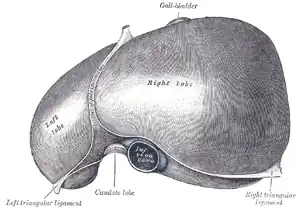

|

| Foie humain, vue supérieure |

On distingue habituellement deux faces au foie :

- une face diaphragmatique, lisse et en forme de dôme qui épouse la concavité du diaphragme ;

- une face viscérale, plane et présentant de nombreux replis de péritoine et des fissures.

La face diaphragmatique est séparée de la face viscérale en avant par le bord inférieur, qui est aigu et dit « tranchant », en regard du rebord costal inférieur, et en arrière par le bord postérieur, qui est plus arrondi.

Le ligament falciforme, issu du mésentère ventral lors du développement embryonnaire, relie le foie à la paroi abdominale antérieure. C'est un repli de péritoine tendu verticalement depuis l'appendice xiphoïde et le diaphragme jusqu'à l'ombilic. Il contient entre ses deux feuillets le ligament rond du foie, vestige de la veine ombilicale qui s'oblitère après la naissance. Ce ligament falciforme est continu avec la capsule de Glisson qui entoure le foie : sur la face antéro-supérieure (face diaphragmatique), il sépare le foie en deux parties gauche et droite, souvent considérées comme des lobes droit et gauche du foie. Sur la face viscérale, le ligament falciforme se continue par la capsule, tandis que le ligament rond qu'il contient s'insère dans la moitié antérieure d'un sillon appelé le sillon sagittal gauche.

On distingue donc au foie deux lobes — gauche et droit — sur la face diaphragmatique du foie, marqué par l'insertion du ligament falciforme. Cette subdivision du foie repose uniquement sur un critère anatomique : on ne devrait pas parler de « lobe », car la lobulation d'une glande repose sur d'autres critères structuraux, notamment la présence de septa conjonctifs qui viennent séparer la glande en plusieurs unités fonctionnelles. Le lobe droit du foie est le plus volumineux, tandis que le lobe gauche est petit et se termine en pointe (apex du foie).

En plus de ces deux lobes principaux, on distingue deux petits lobes à la face viscérale du foie : le lobe caudé et le lobe carré.

Face diaphragmatique

La face diaphragmatique est lisse et convexe. Elle occupe les parties antéro-supérieure et postéro-supérieure du foie. Elle présente dans sa partie postérieure une zone à nu, non péritonisée, appelée l'area nuda, qui la fixe au diaphragme.

En avant, elle est séparée du diaphragme par le récessus subphrénique, une extension de la grande cavité péritonéale. Ce récessus subphrénique est séparé en deux par l'insertion du ligament falciforme à la paroi abdominale antérieure, sur le péritoine pariétal. Le foie est fixé en haut par les ligaments coronaires, qui sont des replis péritonéaux en continuité avec la capsule de Glisson, et donc en continuité avec les ligaments falciformes d'une certaine façon. On distingue deux lames à ces ligaments coronaires par rapport à la zone dépéritonisée qu'elles entourent : une lame antérieure, et une lame postérieure. Aux extrémités supérieures droite et gauche du foie, les deux lames s'adossent et forment les ligaments triangulaires droit et gauche du foie, respectivement.